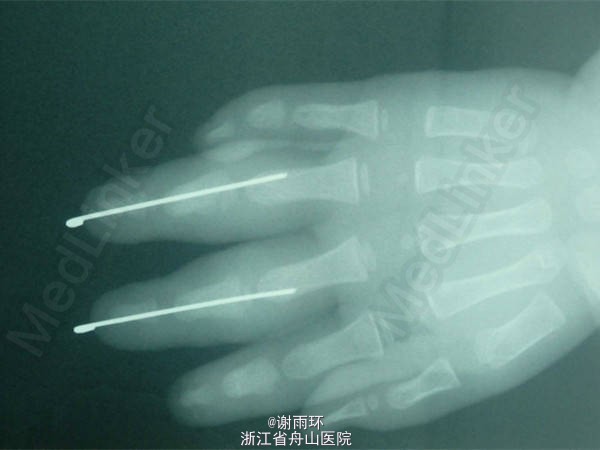

中环指再植

患儿2岁,三角带夹伤致右手中、环指中节基底以远离断。

右手中、环指中节基底以远离断